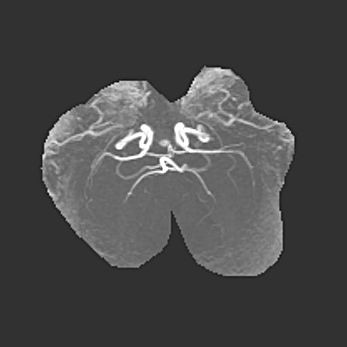

Мальформация Денди-Уокера. Киста задней черепной ямки.

Агенезия мозолистого тела.

Возраст: 2,5 месяца

Вес: 2420 г

Пол: женский

Окружность головы: 37 см

Срок гестации: 32 недели

Мальформация Денди—Уокера — редкий вид патологии ЦНС, представляющий собой врожденный порок развития каудального отдела ствола и червя мозжечка, ведущий к неполному раскрытию срединной (Мажанди) и латеральных (Лушка) апертур IV желудочка мозга. Для этогно синдрома характерна триада симптомов: гипотрофия червя мозжечка и/или полушарий мозжечка, кисты задней черепной ямки, гидроцефалия различной степени. В 70% случаев порок сочетается и с другими аномалиями головного мозга, в частности с агенезией мозолистого тела.